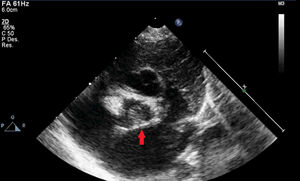

Caso clínicoDatos preoperatoriosRecién nacido a término sin antecedentes gestacionales de interés, diagnosticado de estenosis valvular aórtica a los 2días de vida tras auscultación de soplo cardiaco, con válvula aórtica displásica (fig. 1). En los primeros controles ecocardiográficos se describía una estenosis moderada que, sin embargo, presentó una rápida progresión en las primeras semanas de vida hasta alcanzar criterios de severidad. Se remite al paciente a nuestro centro con gradientes pico/medio por Doppler entre 96/52mmHg y hasta 150/80 según el estudio (fig. 2), sin insuficiencia aórtica y con ventrículo izquierdo (VI) con hipertrofia concéntrica ligera y buena función sistólica. El anillo aórtico era de 7mm, lo que representaba un Z score normal para su peso. Dada la evolución de la estenosis se decide programar la cirugía de forma preferente con el paciente en situación clínica estable.